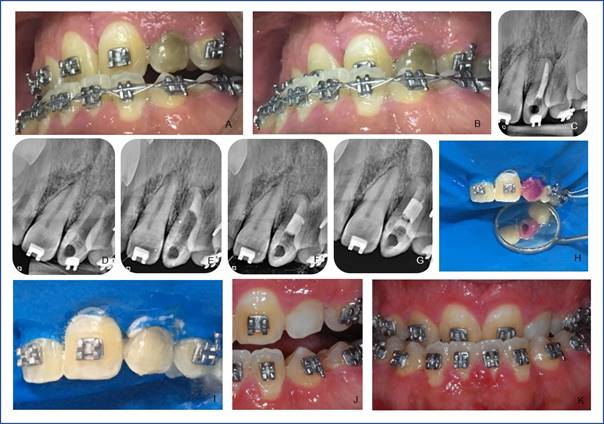

Reporte de Caso Clínico 2: individuo de sexo masculino, 30 años, con Síndrome de Apert, registrado en el HRAC/USP; reportó cambio de color en el diente superior izquierdo (22) (Fig. 2, A y B), observado en el examen clínico, así como también ausencia de sintomatología dolorosa. En la radiografia se observó tratamiento endodóntico insatisfactorio (Figura 2, C). Se realizó el retratamiento endodóntico (Fig. 2, D y E) con necesidad de confección de un tampón apical con MTA (Fig. 2, F) (Angelus Ind. De Produtos Odontológicos S/A, Londrina, PR, Brasil). Transcurridos 6 meses de haber finalizado el retratamiento; fue iniciado el blanqueamiento dental interno mediante la técnica inmediata: el registro del color fue solo la realización de la foto intrabucal (Fig. 2, B), ya que el color del diente no se identificó en la escala VITA (Wilcos do Brasil, Petrópolis, RJ, Brasil) por ser más oscura. Se colocó entonces el aislamiento absoluto, seguido del acceso a la cámara pulpar mediante el uso de la fresa diamantada nº 1012 (KG Sorensen Ind. Com. Ltda, Barueri, Brasil), desobturación endodóntica con condensadores nº 2 entrada del conducto radicular, limpieza de la cavidad y confección del tampón cervical con resina fotopolimerizable surefil SDR flow (Dentsply Ind. Com. Ltda, Petrópolis, RJ, Brasil) (Fig. 2, G). Luego se realizó el ataque ácido de la cámara pulpar con ácido fosfórico 37% (Biodinâmica, Ibiporã, PR, Brasil) durante 30 segundos y se removió con lavado abundante con agua por 60 segundos y secado con chorro de aire. El gel peróxido de hidrógeno 35% (Whiteness HP, FGM, Joinville, SC, Brasil) se manipuló siguiendo las instrucciones del fabricante y colocado en el interior de la cámara pulpar y en la cara vestibular (Fig. 2, H y I) con el auxilio de un microbush tamaño medio (KG Sorensen Ind. Com. Ltda, Barueri, Brasil) con una aplicación de 45 minutos, el gel se removió después del lavado con agua durante 1 minuto, se realizó una segunda aplicación por 25 minutos y se selló con resina surefil SDR flow (Dentsply Ind. Com. Ltda, Petrópolis, RJ, Brasil). En la segunda sesión se realizaron de igual forma el aislamiento absoluto, barrera cervical con Top Dam (FGM, Joinville, SC, Brasil), ataque ácido, lavado y secado, el gel peróxido de hidrógeno 35% (Whiteness HP, FGM, Joinville, SC, Brasil) se manipuló siguiendo las orientaciones del fabricante e insertado en el interior de la cámara pulpar y en la cara vestibular con el auxilio de un microbush tamaño medio (KG Sorensen Ind. Com. Ltda, Barueri, Brasil) realizándose la primera aplicación por 15 minutos, luego de removerse el gel, la segunda aplicación se realizó por igual periodo, solo externamente limitada a la región cervical. Se logró resultado satisfactorio (Fig. 2, J y k) al compararse con el aspecto del inicio del blanqueamiento y restauración provisional con resina surefil SDR flow (Dentsply Ind. Com. Ltda, Petrópolis, RJ, Brasil). En el regreso, el paciente fue referido al sector de Odontología Estética donde fue realizada la restauración definitiva.